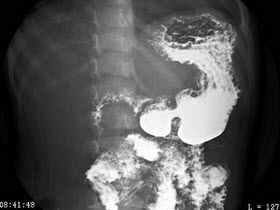

B.骨龄延迟